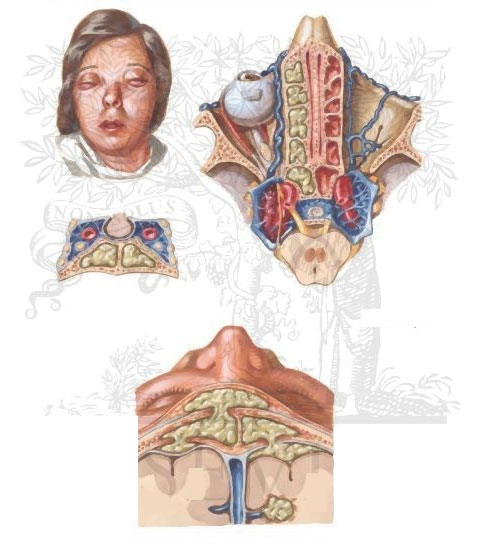

اغلب، عوارض داخل جمجمه با آبسه های واقع در سینوس فرونتال همراه بودند (شکل ۱،۲ الف، ب).

تا آنجا که علائم و نشانه های حنجره، انحراف تیغه ی بینی و پوسیدگی دندان در اکثر بیماران مشاهده شده است. ادم فرانتال در هفت بیمار (۱۴%)، ادم پلک فوقانی در ۴ بیمار (۸%) و در ۸ بیمار (۱۶%) پولیپ قدامی بینی از طریق رینوسکوپی مشاهده شد. تقریباً در همه ی بیماران، غشای مخاطی بینی ملتهب و قرمز بود که اغلب با ترشح مخاطی در زیر مخاط داخلی ظاهر می شد. در دو بیمار (۴%)، سینوزیت حاد پارانازال با اوتیت میانی حاد همراه بود.